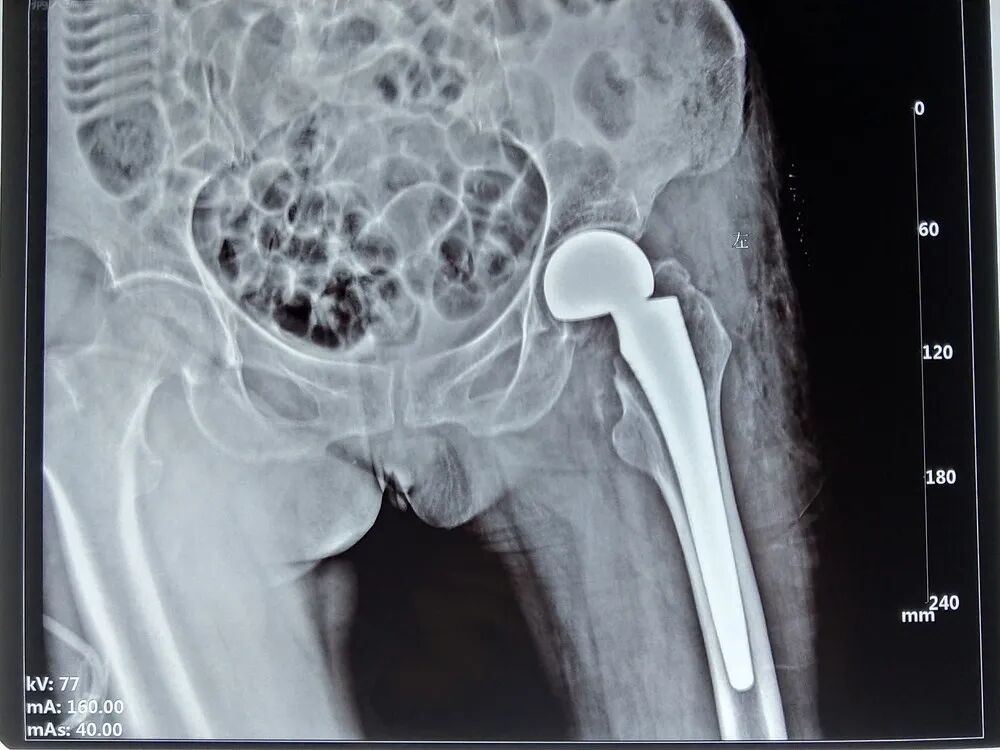

患者左髋部疼痛,肿胀,活动受限,随后到“下街卫生院”就诊,行DR片,左侧股骨颈骨折,随后又到柳位中医正骨医院就诊,行CT片,左侧股骨颈骨折,初步诊断为“左侧股骨颈骨折”。

现病史:6天前,患者下门台时踩空,致左髋部疼痛、肿胀、活动受限,无昏迷、恶心等症状,无胸腹不适,受伤过程能清晰回诉,随后到“下街卫生院”就诊,行DR片,左侧股骨颈骨折,随后又到我院就诊行CT片,左侧股骨颈骨折,为进一步治疗,来我院就诊,门诊以“左侧股骨颈骨折”收入我科。